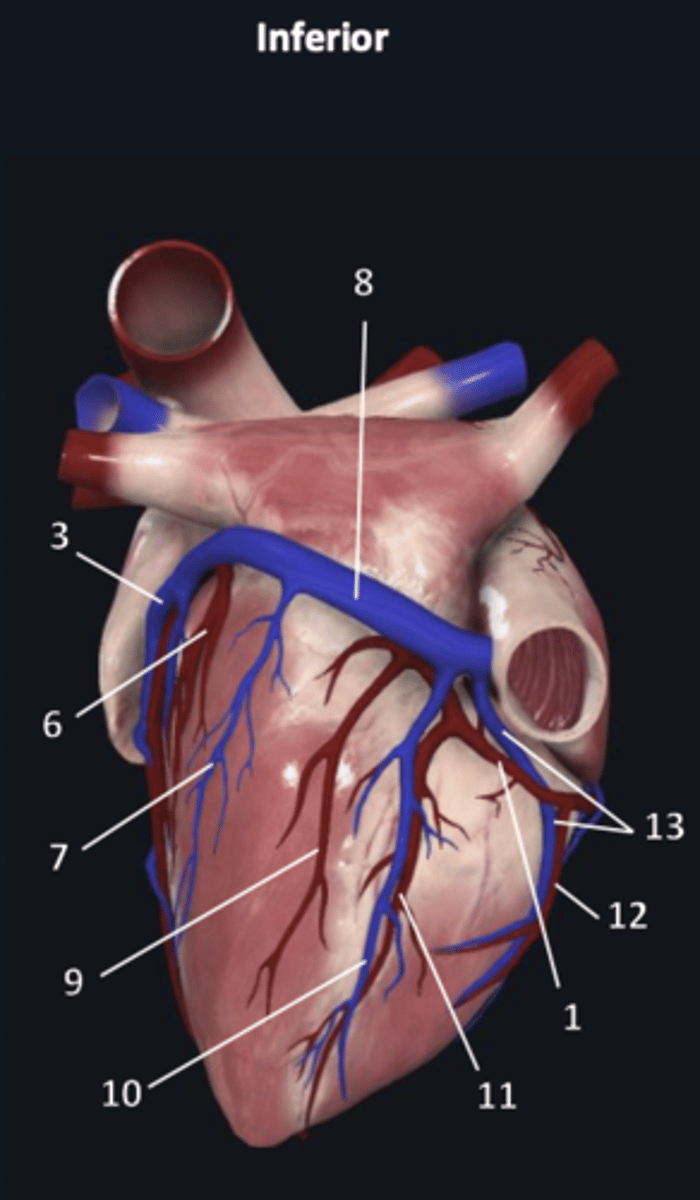

right coronary artery

1

anterior interventricular artery

2 (red)

great cardiac vein

3 (blue)

anterior interventricular artery

2 (red)

great cardiac vein

3 (blue)

left marginal artery

4

left marginal vein

5

posterior left ventricular artery

6

posterior vein of left ventricle

7

coronary sinus

8

right coronary artery

1 (red)

great cardiac vein

3

posterior left ventricular artery

6

posterior vein of left ventricle

7

coronary sinus

8

right posterolateral artery

9

middle cardiac vein

10

posterior interventricular artery

11

right marginal artery

12

small cardiac vein

13